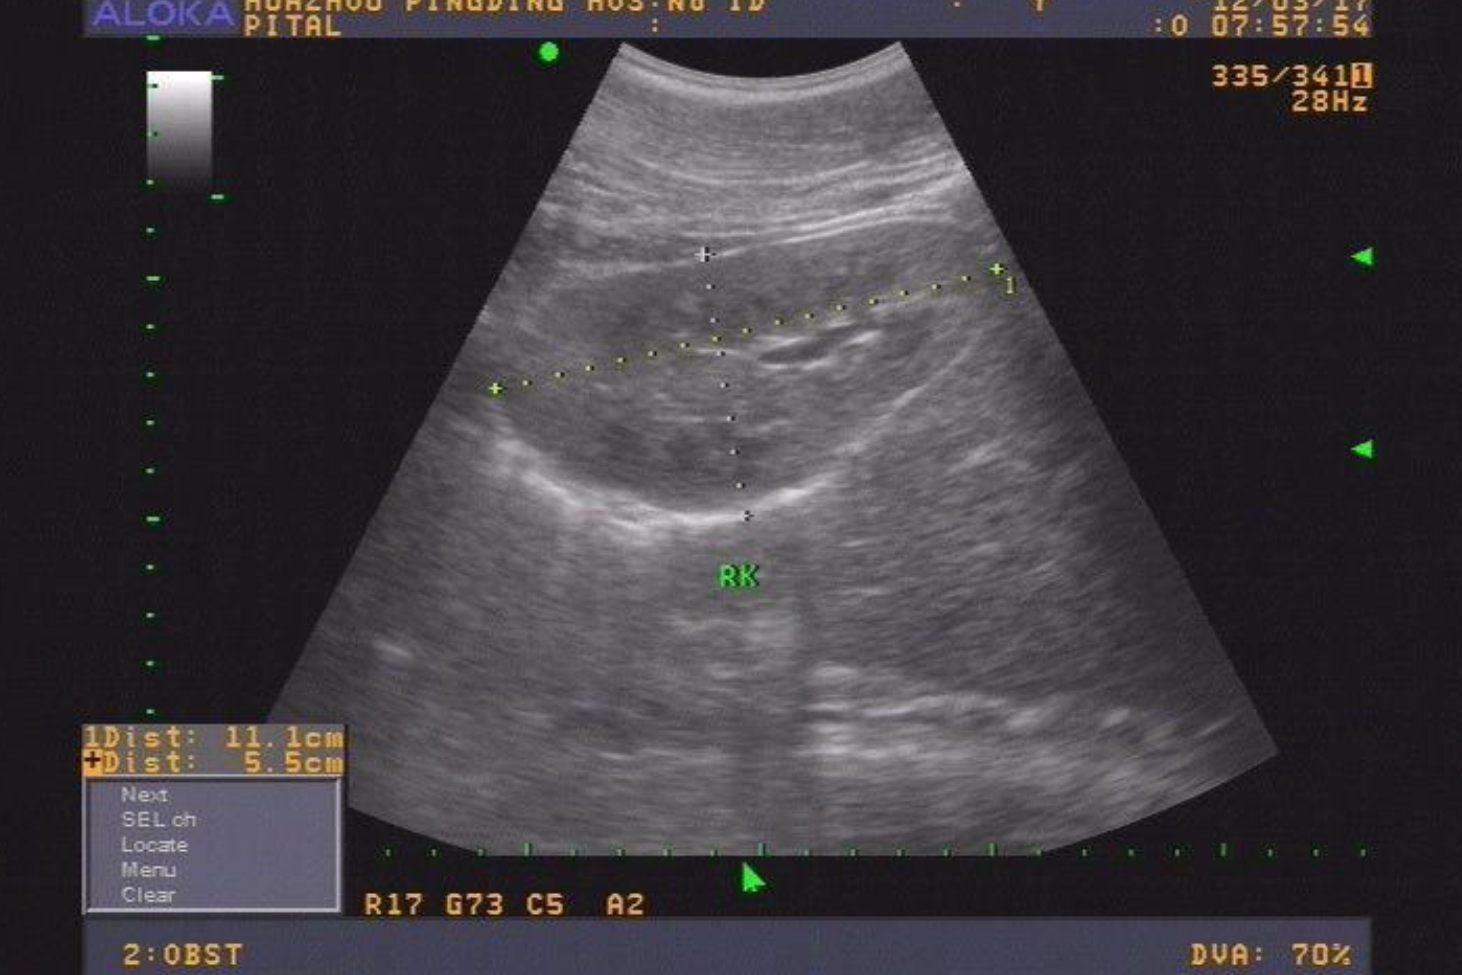

1、双角子宫在二维超声下表现为子宫外形异常,宫底部浆膜层凹陷,轻度者宫底呈弓状或者马鞍状,严重者比较深,但凹陷的深度一般大于1厘米,宫腔在内口以上处分离,形成两角状突起,称为不全双角子宫。

2、在二维超声上纵切面表现不明显,横切面上内口处宫腔形态正常,在逐渐向宫腔底部移动的过程中,可见到以等回声的隔将宫腔分开,膈的宽度也逐渐增大,宫腔在内口处分离成为完全双角子宫。